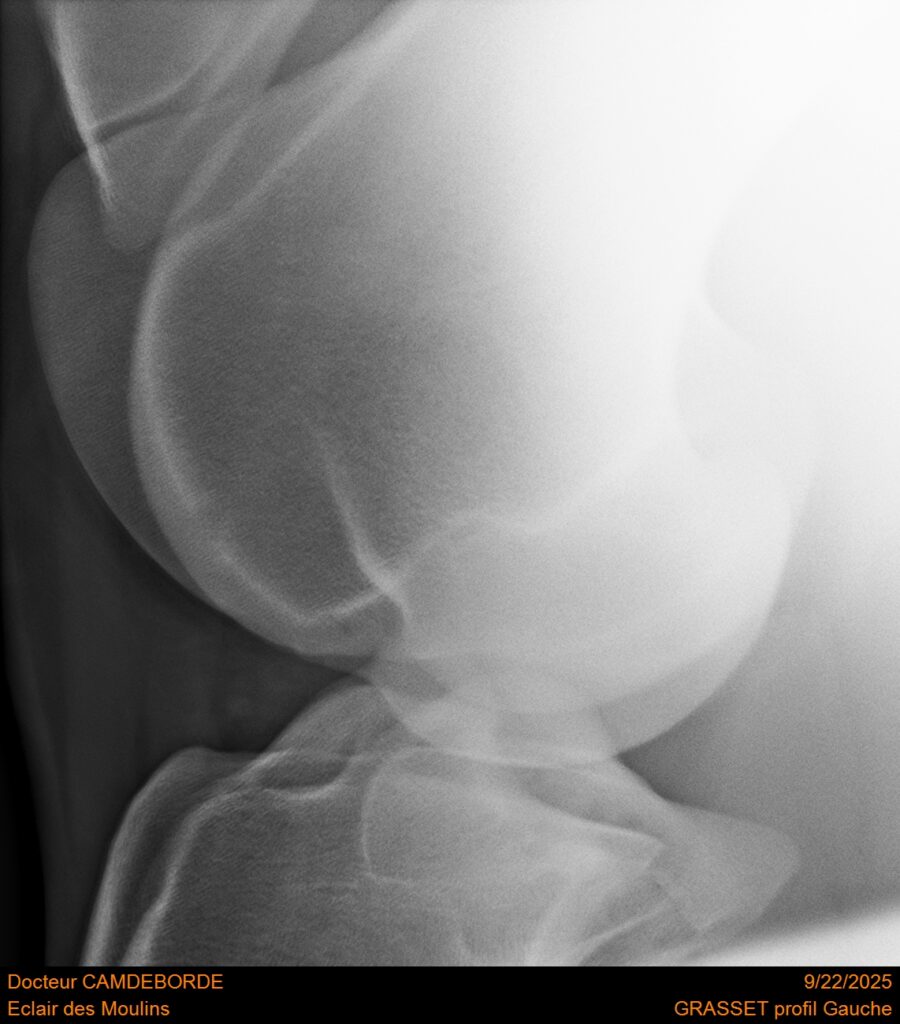

10 K ✨ TOP cheval pour épreuve Amateur ! ECLAIR DES MOULINS, selle Français de 11 ans. Classé sur 1m05. Idéal pour aller faire jusqu’à 110 voir 115, cheval pas usé (une vingtaines de parcours). Très gentil au quotidien, cheval de famille. Courageux et respectueux à l’obstacle. Bien dressé, change de pieds. Bilan pieds, boulets, jarrets, grassets et visite clinique effectuée cette semaine. il peut vivre au box comme au champs, cheval rustique. toise environ 1m60 porteur. Pour le compte de son propriétaire car manque de temps.

RADIOS ET CLINIQUE